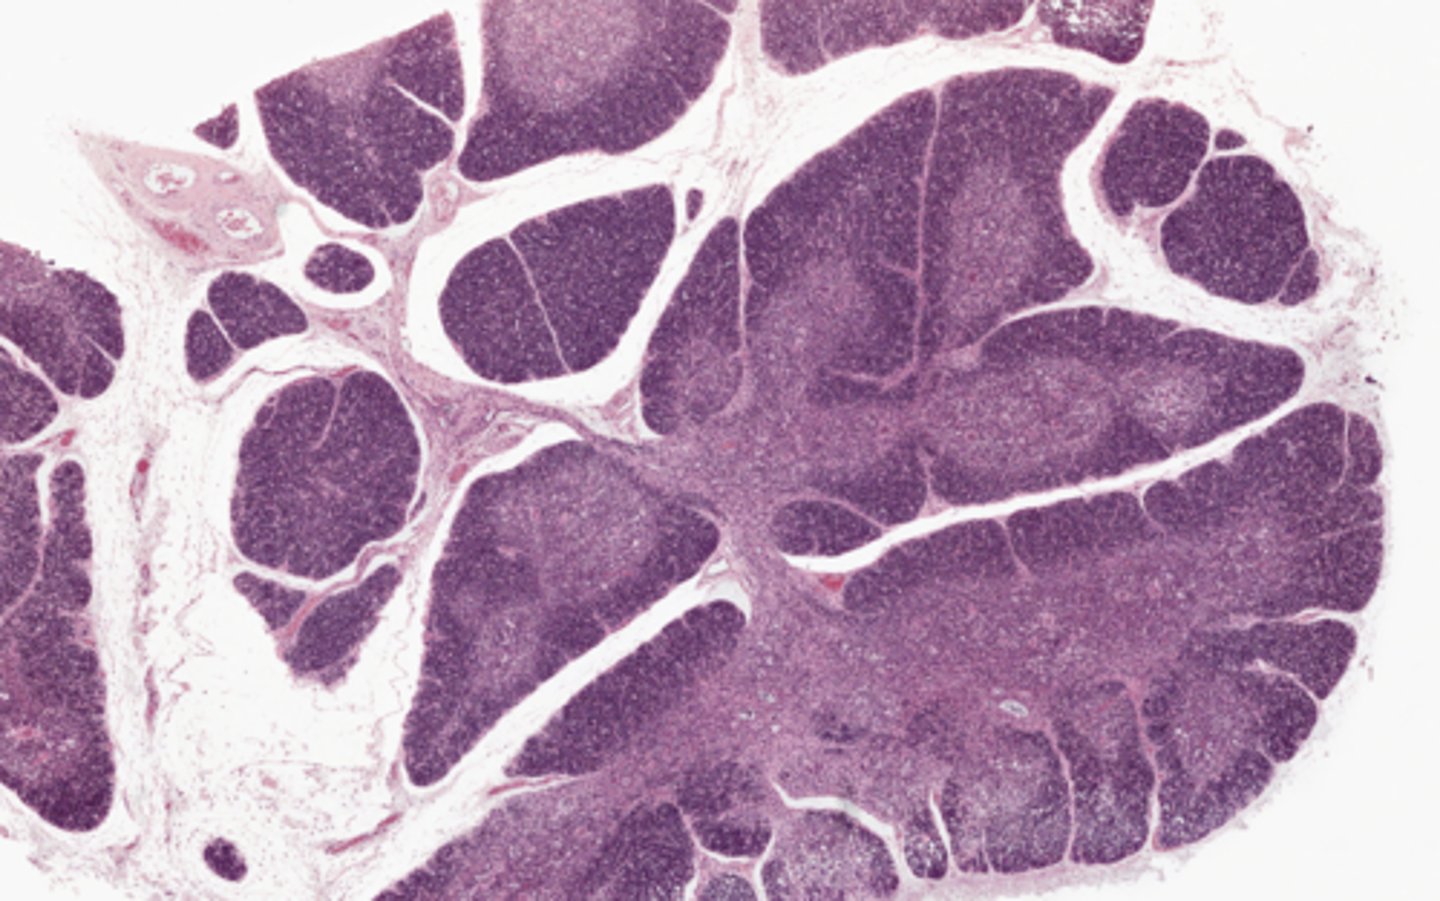

Thymus